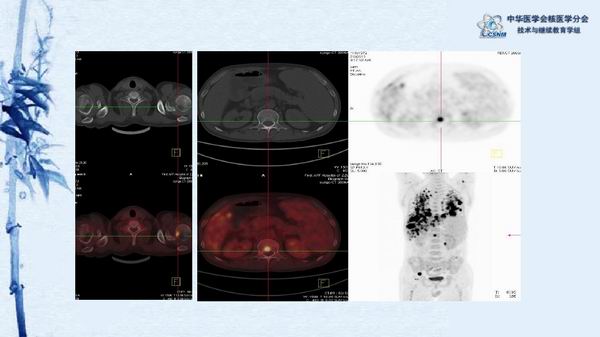

病例49:PET-CT显像诊断淋巴瘤相关噬血细胞综合征一例-【CSNM继教学组】程兵 郑州大学第一附属医院